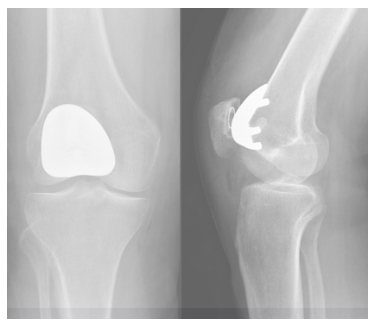

The patellofemoral prosthesis or the kneecap prosthesis is a kind of half knee prosthesis for people with isolated wear to the patellofemoral joint. The advantages are the same as for the half knee prosthesis: a large part of your own knee, including the tibiofemoral joint and the cruciate ligaments can be preserved.